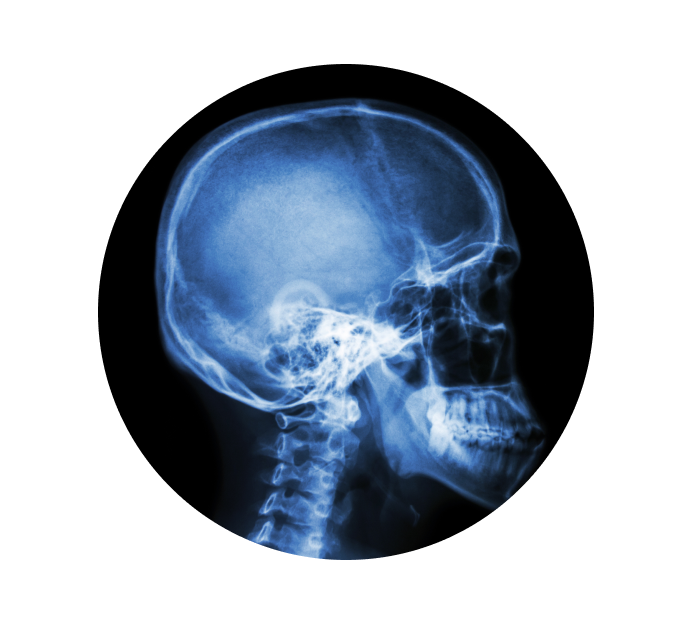

Рентген турецкого седла в Сочи

Турецкое седло — это костное образование, которое находится в середине черепной коробки и защищает гипофиз (железа, вырабатывающая гормоны, участвующие в процессах обмена веществ, роста и развития человеческого организма). Рентген турецкого седла делается по назначению врача для того, чтобы определить присутствие патологий. Снимок может показать форму, структуру и размеры седла, что позволит доктору определить присутствие возможных заболеваний.